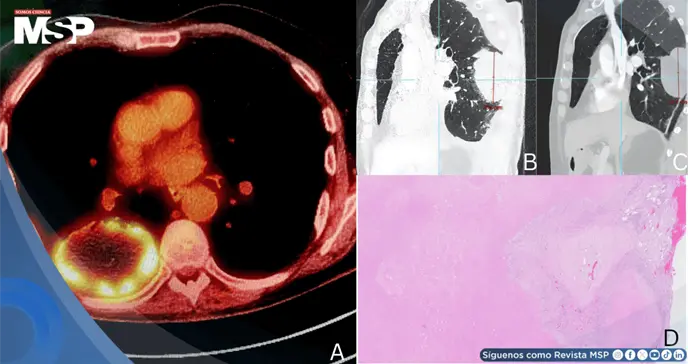

Este hallazgo dio paso a una evaluación más amplia mediante tomografía computarizada (TC) de tórax, abdomen y pelvis, donde se identificó una lesión de gran tamaño —75 x 50 mm— ubicada en la porción posterior del lóbulo inferior derecho, como se aprecia en la Figura 1A.

Con el fin de caracterizar mejor la masa, se realizó un PET-CT que evidenció una elevada actividad metabólica (SUVmax 13.5), sin compromiso de ganglios linfáticos ni evidencia de metástasis a distancia.

El tejido resecado mostraba un 90% de necrosis y un 10% de estroma fibrótico, con todos los ganglios linfáticos libres de malignidad, como se observa en la Figura 3. El aparente crecimiento tumoral durante la terapia se interpretó entonces como un caso de pseudoprogresión.